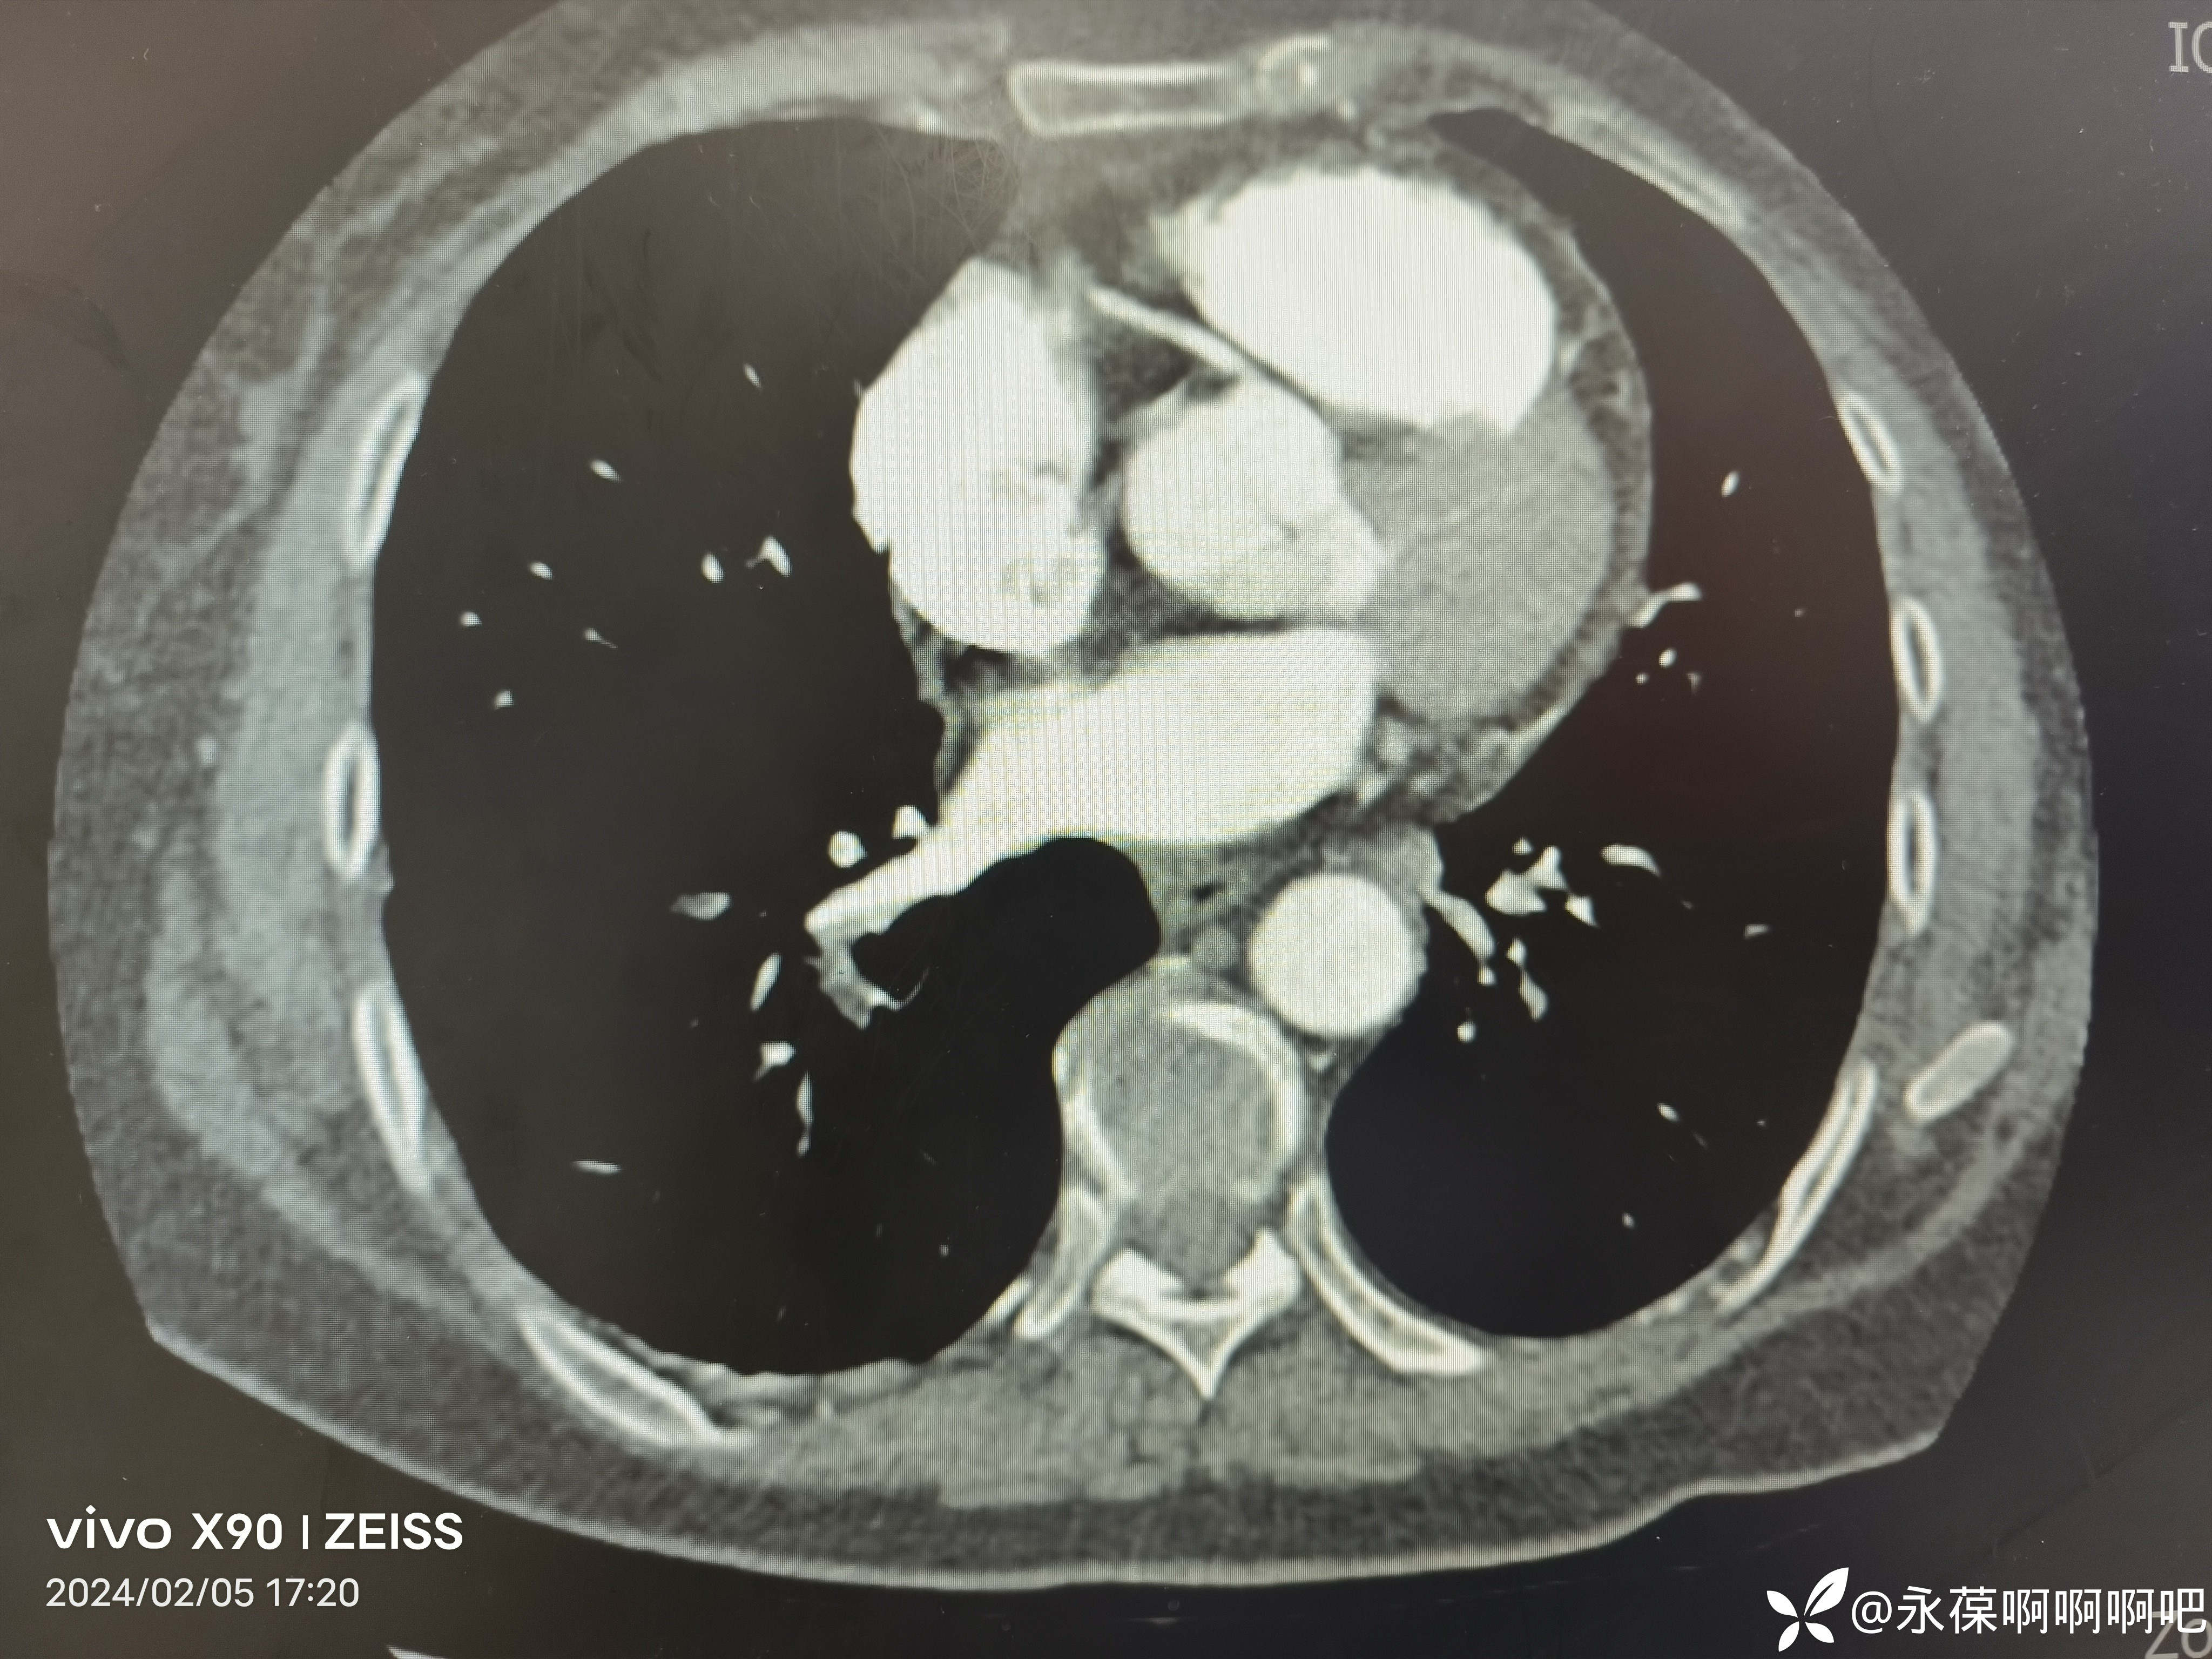

肺动脉CTA:左右肺动脉干及其分支多发栓塞。